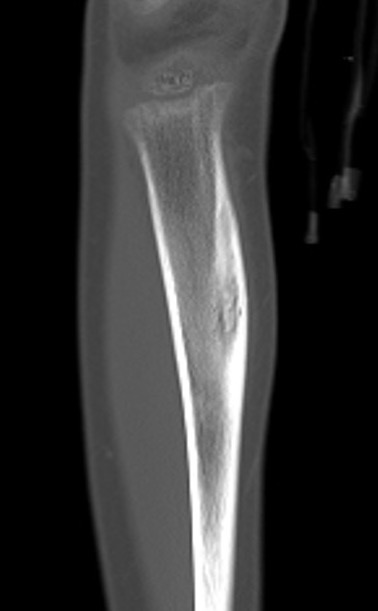

CT

Can be used to differentiate from osteochondroma

1. Parosteal OS

- attached to cortex growing into soft tissue

- normal cortex intact

Parosteal Osteosarcoma proximal tibia